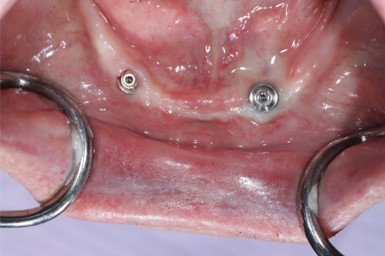

Prosthodontics (also known as dental prosthetics or prosthetic dentistry) is one of the nine dental specialties recognized by the American Dental Association (ADA). Prosthodontists specialize in the diagnosis, restoration, and replacement of missing teeth.

Extensive training and experience give prosthodontists a unique understanding of restoring the dynamics of a smile and healthy mouth with the creation of tooth prostheses. Becoming a prosthodontist requires an additional three years of specialty training after obtaining a DMD (Doctor of Dental Medicine) or DDS (Doctor of Dental Surgery) degree.